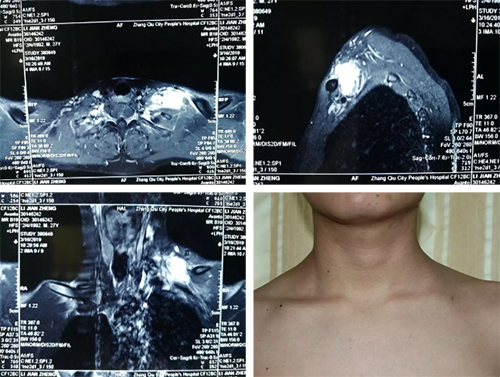

一开始做了些检查,但却搞不清楚看哪个专业对症。他先是住进了普外两腺科病房,怀疑是甲状腺或淋巴结肿瘤,可又都不像。做了MRI以及穿刺病理检查,MRI提示“肿瘤”位于锁骨上臂丛神经区域,来源于臂丛神经的可能性较大;穿刺病理则提示没有神经来源肿瘤证据,也不是来自甲状腺和淋巴结的肿瘤。

经过反复检查,审视小李的每个体征,官士兵和团队不放过一块肌肉、一条神经、一片感觉支配区域。在磁共振室,与影像科专家一帧一帧研究图像,反复推敲;在超声室,与肌骨超声专家亓恒涛主任从各个方向仔细探究、分析。通过在MRI与超声检查之间相互对照、印证,官士兵最后推断“肿瘤”位于左侧前斜角肌,主要应该在臂丛神经的外面。鉴于“肿瘤”边界不清楚,可能与周围组织粘连,极易在手术剥离过程中伤及周围组织,比如锁骨下静脉、锁骨下动脉、臂丛神经、胸膜顶、颈动脉鞘、膈神经等。

小李术前磁共振图片。